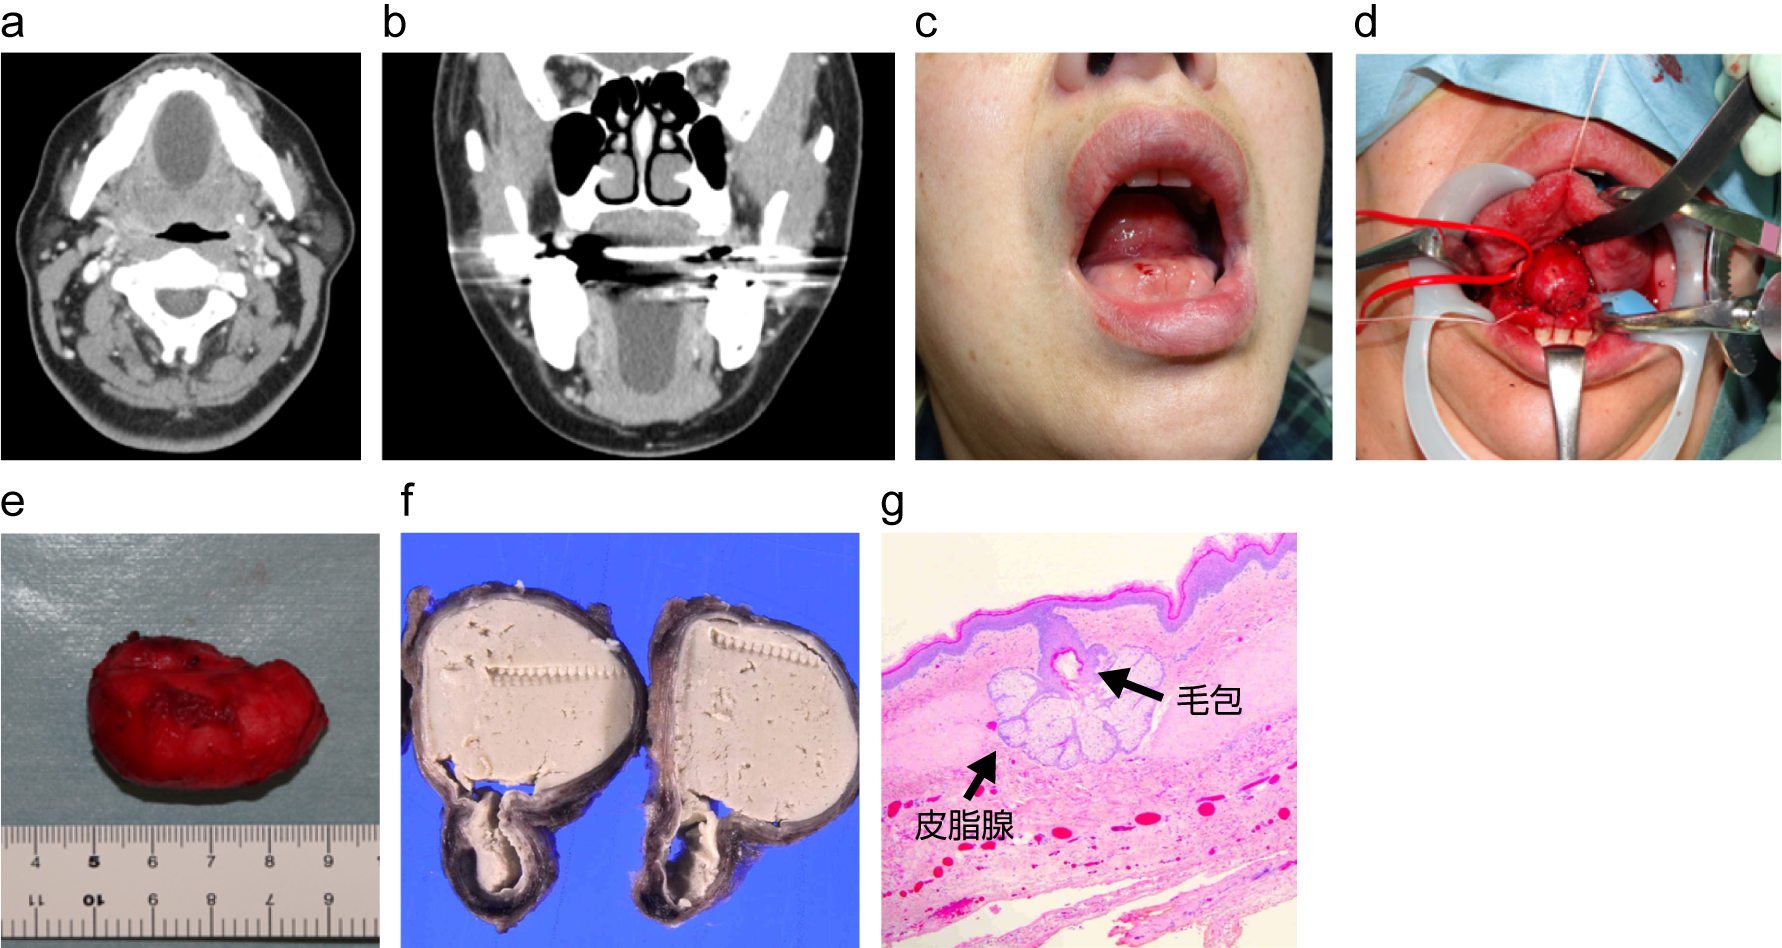

症例3:皮様嚢腫

a:術前CT画像 軸位断、b:術前CT画像 冠状断、c:術前口腔底所見、d:摘出途中の画像、

e:摘出標本、f:病理検体断面像、g:HE染色

出典

img

1: 著者提供